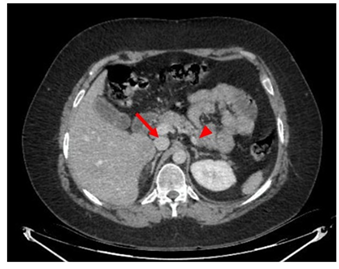

A 33-year-old man with a history of psychiatric pathology treated with risperidone since childhood. In the previous three years, he presented multiple episodes of symptomatic hypoglycaemia that required hospital admission and management with continuous infusion of glucose serum, with blood glucose values that reached 35 mg/dl, seizures and loss of consciousness, which require management in intensive care. During the evaluation, a computed tomography of the abdomen was requested, which showed 2 pancreatic lesions, one in the body of 28 mm and another in the uncinate process of 42 mm. Additionally, multiple focal lesions were found in the liver, the largest of which was 32 mm (Figure 1). Likewise, venous glycemia of 37 mg/dl, insulin of 137 (normal range 2 to 12 μU/mL) and increased C-peptide of 8.27 (normal range 1.1 to 4.4 ng/ml) were found, which allowed a diagnosis of malignant insulinoma with liver metastases. A PET-CT scan with 18F-NOTATOC confirmed that pancreatic and hepatic lesions expressed somatostatin receptors (Figure 2a and 2b).

Figure 1: Axial computed tomography scan. Insulinoma is observed on the right in the uncinate process (arrow) and on the left (arrowhead)